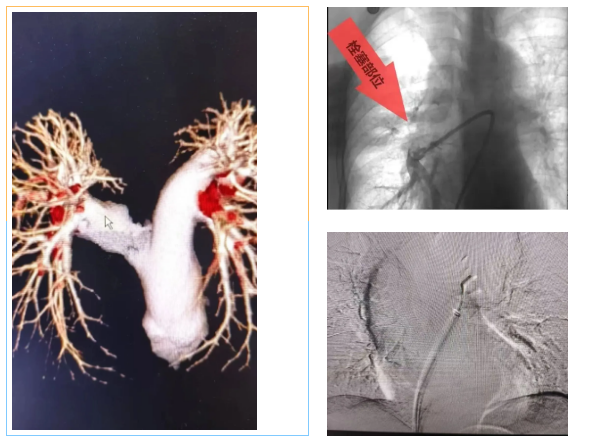

近日,洛阳白马医院内二科与介入科团队成功为一名74岁的高危肺栓塞患者实施了联合介入治疗。该患者高龄、血栓负荷重,且血小板水平较低,病情复杂、风险较高。面对这一挑战,内二科与介入科医生共同制定了适合患者个体条件的介入方案,由介入科独建库主任在DSA(数字减影血管造影)引导下,依次完成肺动脉造影、血栓抽吸、静脉滤器植入,并配合抗凝治疗。整个手术采用微创方式,术后患者状态平稳,症状明显改善,目前已进入后续康复阶段。

值得一提的是,此次治疗是内二科成功开展的首例肺动脉介入治疗(肺动脉造影+血栓抽吸),标志着科室在肺血管疾病微创诊疗方面迈出了重要一步。

• 介入取栓:微创,用导管直接把血栓抽出来,见效快——本案例采用的就是这种方法。

• 静脉滤器植入:在血管里放一个“小网兜”,拦住脱落的血栓,防止再次发生肺栓塞。